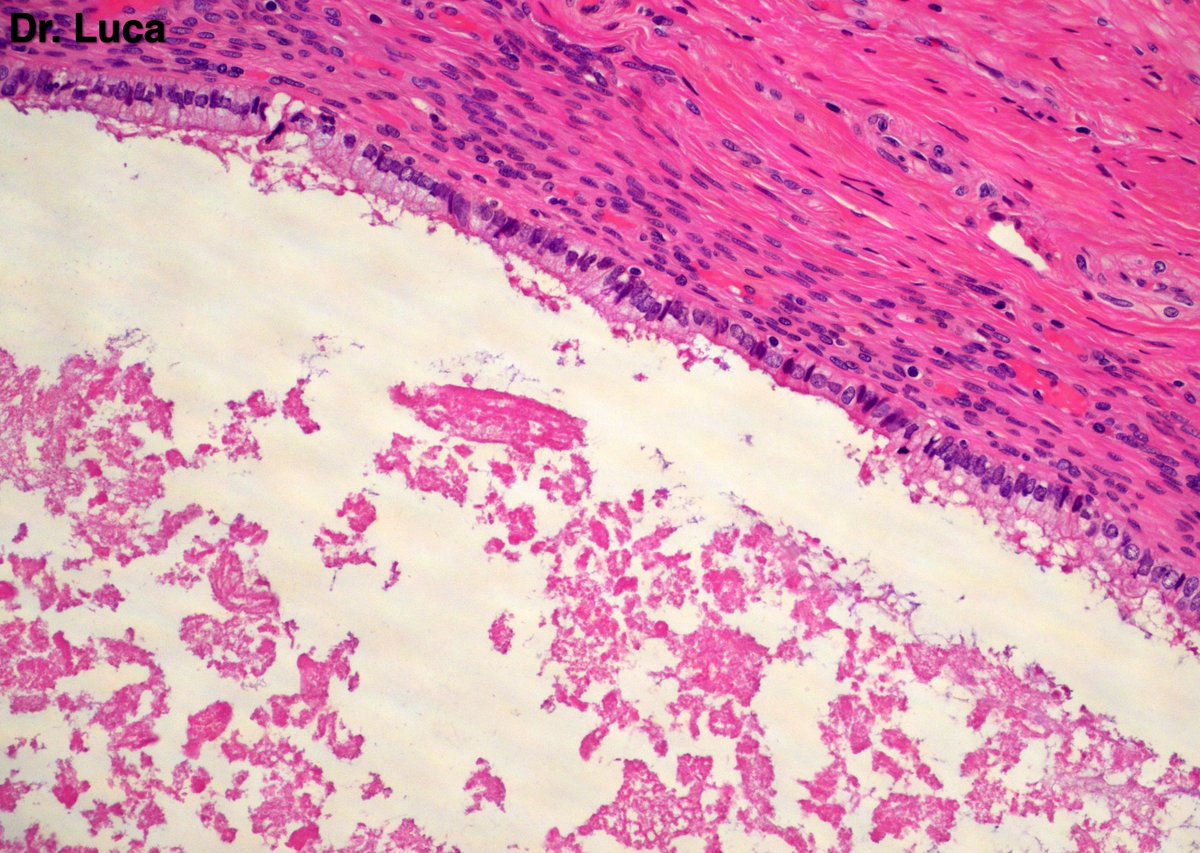

Ok that's a seminal vesicle! you can see very well the secretory cells, many of them harboring intracytop. pigment and in some images you can also note the basal cells...at the apex of this seminal vescicle I found a 2.5 cm multilocular cystic lesion, how do you call it? #gupath